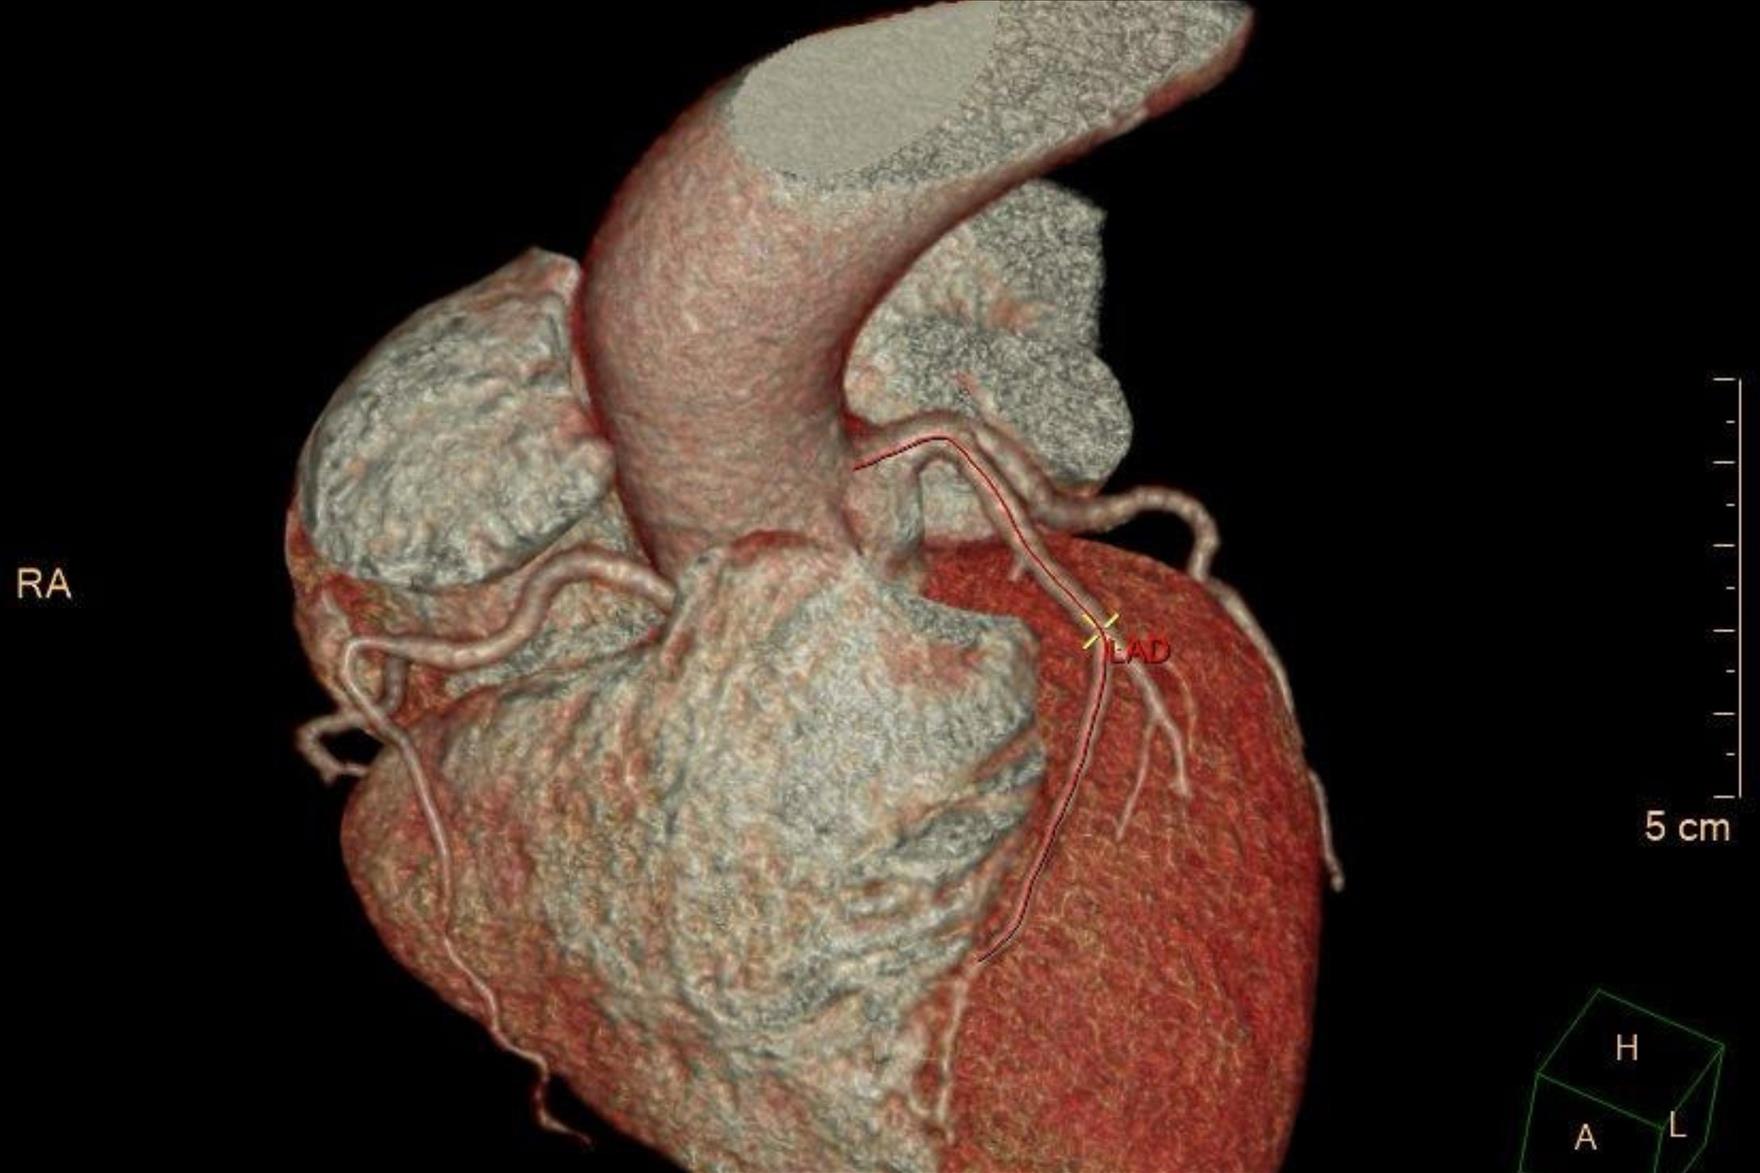

PAÜ Hastaneleri Radyoloji Anabilim Dalı Öğretim Üyesi Doç. Dr. Vefa Çakmak yaptığı açıklama da şunları söyledi: “Pandemi döneminde hayatımıza daha sık giren bilgisayarlı tomografi (BT), günümüzde tanı ve tedavi süreçlerinde hayati önem taşıyan bir görüntüleme yöntemi olarak kullanılmaya devam ediyor. Radyasyon içeren bu teknoloji, pek çok organın ayrıntılı şekilde incelenmesini sağlarken, acil durumlarda hızlı teşhis imkânı sunarak hayat kurtarıcı bir rol üstleniyor. Özellikle kanserin tanı ve takibinde, trafik kazaları, beyin kanamaları, kırıklar ve büyük cerrahiler öncesinde önemli bir yer tutuyor. BT ile kalbi besleyen damarların detaylı şekilde görüntülenmesi mümkün hale geliyor. Halk arasında ‘sanal anjiyo’ olarak bilinen bu yöntemle, kalpte işlem gerektiren damar tıkanıklıkları erkenden saptanabiliyor. Böylece hastalar, gereksiz klasik anjiyo işlemlerinden korunuyor. Aynı anda kalp duvarları, kalp içindeki pıhtı ya da tümör gibi oluşumlar ve ritim bozukluğuna neden olabilecek yapılar da değerlendirilebiliyor. Ayrıca, bu çekimler sırasında düşük dozla akciğer görüntülemesi de yapılarak yapısal akciğer hastalıkları, akciğer kanserleri ve göğüs kafesiyle ilgili kemik problemleri de tespit edilebiliyor. Çekim öncesinde hastanın böbrek fonksiyonlarını korumak amacıyla kreatin ve GFR gibi kan testleri yapılıyor. Hastanın mevcut hastalık öyküsü ve ilaç alerjileri sorgulanıyor. Kaliteli bir görüntü elde edebilmek için kalp atım hızının dakikada 70 civarına düşürülmesi gerekebiliyor; bu durumda nabız düzenleyici ilaçlar kullanılabiliyor. İşlem sırasında hasta monitörize ediliyor, göğüs bölgesindeki metal eşyalar çıkarılıyor ve yaklaşık 10–15 saniyelik nefes tutması isteniyor. Kardiyak BT çekimi 4–10 saniye sürüyor ve görüntülerin değerlendirilip raporlanması genellikle aynı gün içinde tamamlanıyor.”